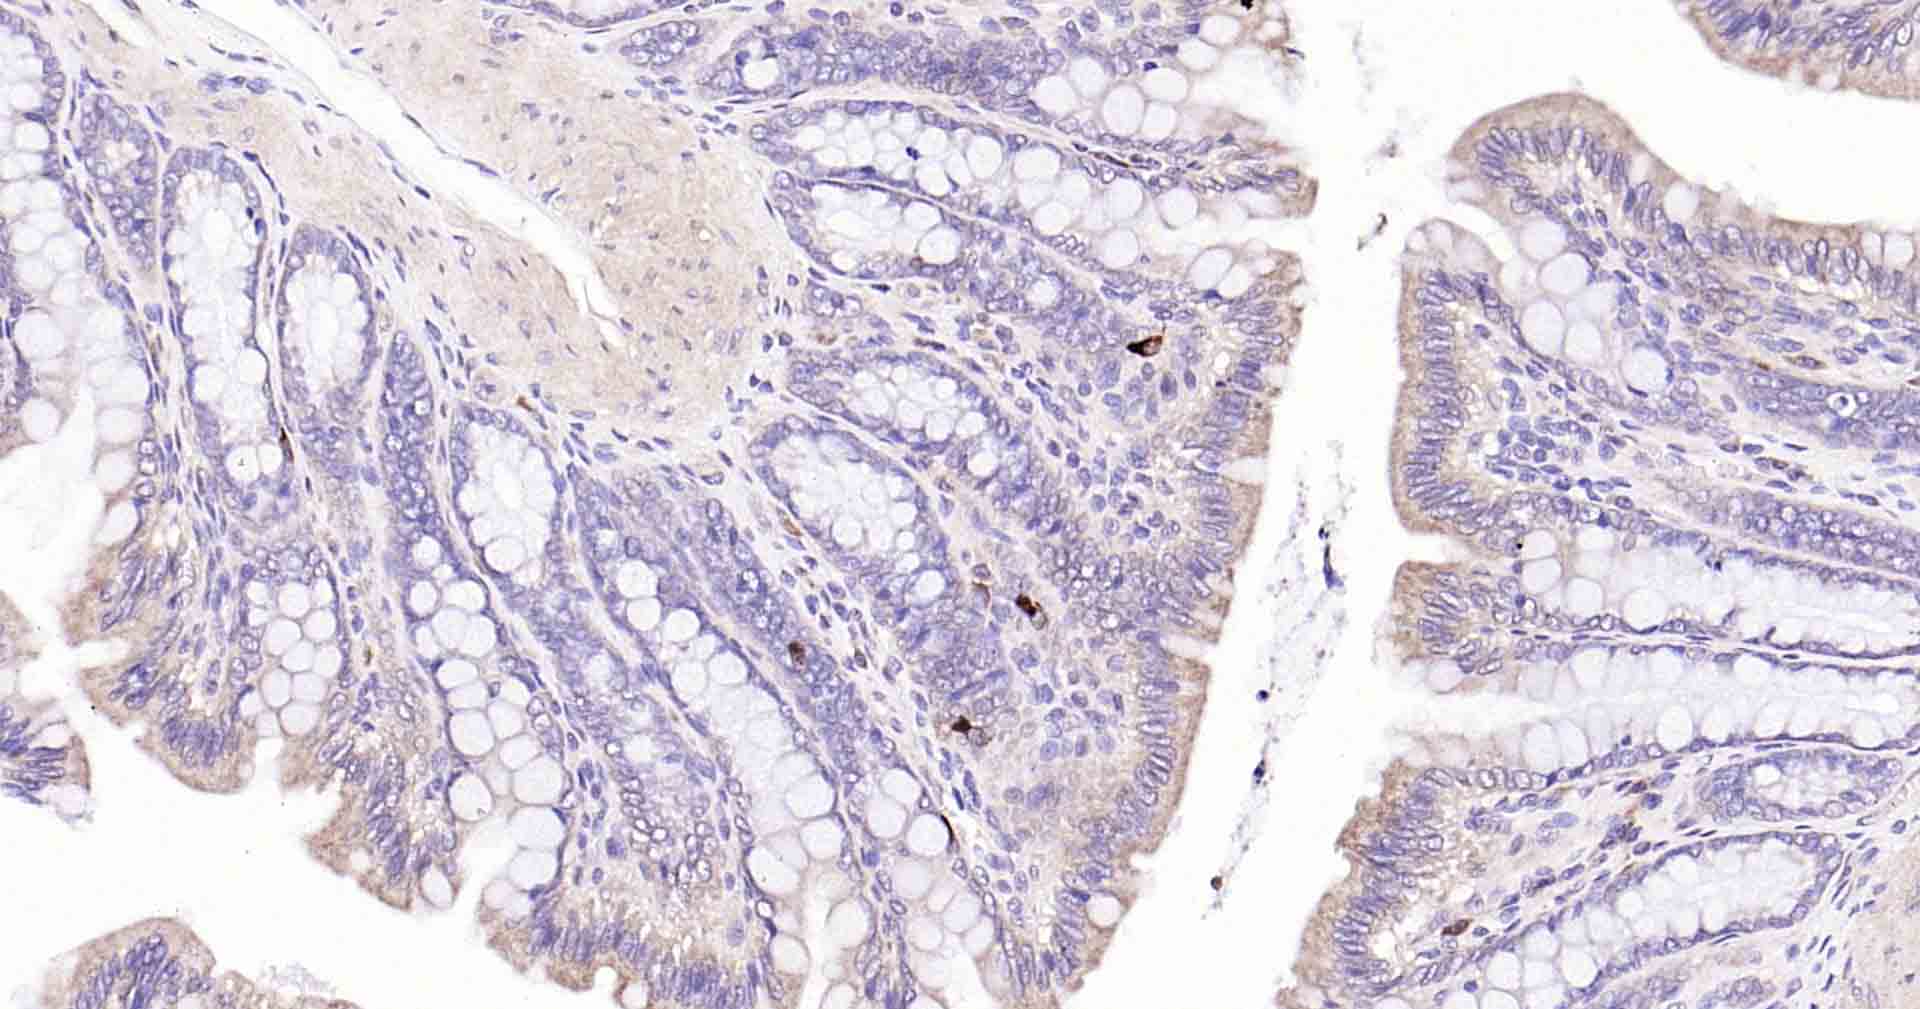

Paraformaldehyde-fixed, paraffin embedded Human Colon; Antigen retrieval by boiling in sodium citrate buffer (pH6.0) for 15 min; Antibody incubation with Beclin 1 Monoclonal Antibody, Unconjugated(bsm-41365R) at 1:50 overnight at 4°C, followed by conjugation to the SP Kit (Rabbit, SP-0023) and DAB (C-0010) staining.